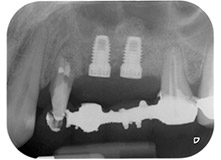

Una paziente donna di 58 anni lamentava dolore e aumentata mobilità del dente di appoggio del ponte 24. Era presente infiammazione periodontale con tasche di profondità di 7 mm a livello mesiobuccale e di più di 12 mm a livello distale, nonché coinvolgimento di terzo grado della forcazione. Inoltre, la radiografia rivelava una lesione periodontale estensiva attorno alla regione apicale del dente pretrattato 24 (in altro luogo) a livello endodontico (Fig. 1).

Tutto il tessuto osseo vestibolare e distale era mancante in corrispondenza della radice buccale. La possibilità di attacco era essenzialmente ristretta alla radice palatale, evidenziando la prognosi negativa preliminare. Anche il dente 27 mostrava un punto di attacco orizzontale ridotto e una rarefazione apicale minima (cfr. Fig. 1), senza sintomi clinici.